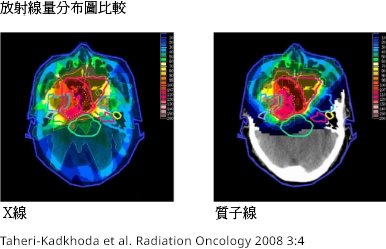

頭頸部腫瘤的放射治療案例。 紅框包圍的部分

是腫瘤。 紅色表示輻射劑量強,從黃色到藍色減

弱。 與 X 射線(左)相比,質子射線(右)在腫瘤

周圍的輻射劑量集中,頭後部的輻射劑量接近於零